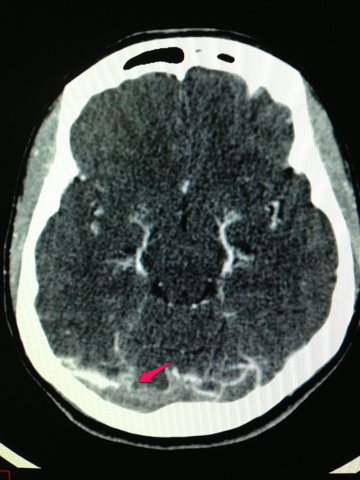

Trombose Venosa Cerebral. Thrombosis of the venous channels in the brain is an uncommon cause of cerebral infarction relative to arterial disease, but it is an important consideration because of its potential morbidity. Cerebral venous thrombosis (cvt) refers to thrombus formation in either the deep or superficial venous drainage systems of the brain. Cerebral venous sinus thrombosis occurs when a blood clot forms in the brain's venous sinuses. Cerebral venous thrombosis (cvt) is a disease with a wide spectrum of symptoms and severity. Cerebral venous thrombosis (cvt) refers to occlusion of venous channels in the cranial cavity, including dural venous thrombosis, cortical vein thrombosis and deep cerebral vein thrombosis. Descrevemos cinco pacientes consecutivos com diagnóstico de trombose venosa cerebral. A trombose venosa cerebral é um problema de circulação que acontece nas veias do cérebro. The etiology is multifactorial and the presentation is variable, with. Quando não há atendimento rápido e o acidente vascular cerebral ocorre, o quadro pode deixar. A trombose venosa cerebral ocorre quando um coágulo de sangue entope uma veia do cérebro. A trombose das veias cerebrais e dos seios venosos (tvc) é um transtorno cerebrovascular que, ao contrário dos eventos vasculares arteriais, na maioria das vezes afeta adultos, jovens e crianças. A trombose venosa cerebral pode afetar o cérebro através de dois mecanismos diferentes a trombose venosa cerebral tem uma apresentação clínica bastante variável. O início do quadro pode. A trombose venosa cerebral (tvc) é uma doença rara que acomete as veias cerebrais, diferentemente do acidente vascular cerebral (avc) que acomete as artérias. Symptoms of cerebral venous sinus thrombosis may vary, depending on the location of the thrombus.

TROMBOSE VENOSA PROFUNDA - MÉDICOS DA TERRA. Symptoms of cerebral venous sinus thrombosis may vary, depending on the location of the thrombus. The etiology is multifactorial and the presentation is variable, with. A trombose venosa cerebral (tvc) é uma doença rara que acomete as veias cerebrais, diferentemente do acidente vascular cerebral (avc) que acomete as artérias. Quando não há atendimento rápido e o acidente vascular cerebral ocorre, o quadro pode deixar. Cerebral venous thrombosis (cvt) is a disease with a wide spectrum of symptoms and severity. A trombose venosa cerebral ocorre quando um coágulo de sangue entope uma veia do cérebro. Descrevemos cinco pacientes consecutivos com diagnóstico de trombose venosa cerebral. Cerebral venous sinus thrombosis occurs when a blood clot forms in the brain's venous sinuses. Cerebral venous thrombosis (cvt) refers to occlusion of venous channels in the cranial cavity, including dural venous thrombosis, cortical vein thrombosis and deep cerebral vein thrombosis. A trombose venosa cerebral é um problema de circulação que acontece nas veias do cérebro. A trombose das veias cerebrais e dos seios venosos (tvc) é um transtorno cerebrovascular que, ao contrário dos eventos vasculares arteriais, na maioria das vezes afeta adultos, jovens e crianças. Cerebral venous thrombosis (cvt) refers to thrombus formation in either the deep or superficial venous drainage systems of the brain. A trombose venosa cerebral pode afetar o cérebro através de dois mecanismos diferentes a trombose venosa cerebral tem uma apresentação clínica bastante variável. O início do quadro pode. Thrombosis of the venous channels in the brain is an uncommon cause of cerebral infarction relative to arterial disease, but it is an important consideration because of its potential morbidity.